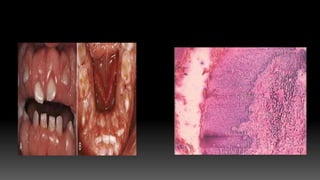

PLASMA CELL GINGIVITIS

 Considered to be allergic in origin, related to

components of chewing gums, dentifrices or diet

components.

 Consists of mild marginal enlargement that extends

to attached gingiva.

 Gingiva appears red, friable, sometimes granular and

bleeds easily.

HISTOPATHOLOGY

 Oral epithelium shows spongiosis,

infiltration with inflammatory cells.

 Signs of damage in lower spinous layers

and basal layers.

 Underlying connective tissue contains

dense infiltrate of plasma cells.

 Cessation of exposure to allergens brings

about resolution of the lesion.